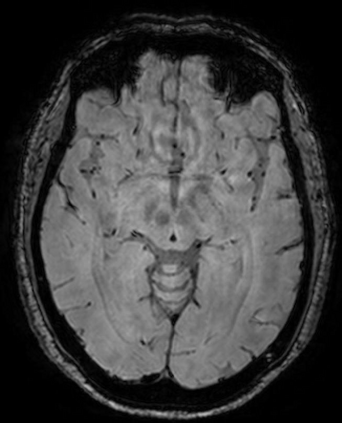

The use of deep learning techniques for 3D brain vessel image segmentation has not been as widespread as for the segmentation of other organs and tissues. This can be explained by two factors. First, deep learning techniques tend to show poor performances at the segmentation of relatively small objects compared to the size of the full image. Second, due to the complexity of vascular trees and the small size of vessels, it is challenging to obtain the amount of annotated training data typically needed by deep learning methods. To address these problems, we propose a novel annotation-efficient deep learning vessel segmentation framework. The framework avoids pixel-wise annotations, only requiring patch-level labels to discriminate between vessel and non-vessel 2D patches in the training set, in a setup similar to the CAPTCHAs used to differentiate humans from bots in web applications. The user-provided annotations are used for two tasks: 1) to automatically generate pixel-wise labels for vessels and background in each patch, which are used to train a segmentation network, and 2) to train a classifier network. The classifier network allows to generate additional weak patch labels, further reducing the annotation burden, and it acts as a noise filter for poor quality images. We use this framework for the segmentation of the cerebrovascular tree in Time-of-Flight angiography (TOF) and Susceptibility-Weighted Images (SWI). The results show that the framework achieves state-of-the-art accuracy, while reducing the annotation time by up to 80% with respect to learning-based segmentation methods using pixel-wise labels for training